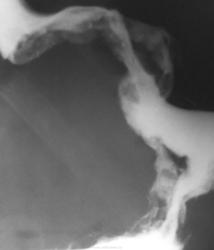

Всего 4 снимка? Могу ошибаться, но впечатление, что желудок вовлечен вторично.

Создалось и у меня такое впечатление уважаемая Любовь.

И почему так деформирован и смещен вверх?

Сомневаюсь, что желудок вторичный. Где газовый пузырь? Может быть из чего-то и выросло, но мы этого не видим. Судмедэксперт вынесет свой вердикт.

Мне тоже показалось, что желудок именно смещен и деформирован каким-то образованием.

Как хотите, коллеги - типичный рак желудка. И аналогопатам (с) тут не поможет: если пациент из р-аппарата вышел, то и секционного стола избежит.

Рак кардиального отдела желудка, распространяется по малой кривизне, практически тотальное поражение. Жаль очень человека, но если нет нигде вторичного, то, может, поживет год после гастрэктомии и химии.

Пациент не прожил год...

Экзитус через 4 дня после исследования..., повезли на консультацию в ООД..., вот прямо там, на поликлиническом приёме...